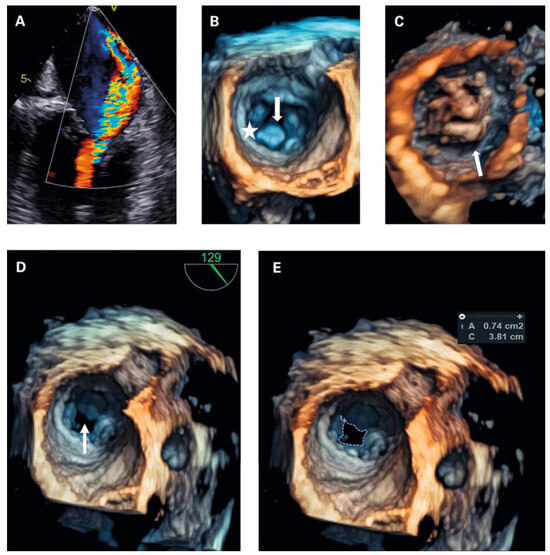

Hemoptysis and Unintentional Weight Loss in a 46-Year Old Patient—Always a Pulmonary Problem?

by Tobias Höfflinghaus, Lena Gerstner, Stephan Wieser and Matthias Meyer

Cardiovasc. Med. 2022, 25(2), 48; https://doi.org/10.4414/cvm.2022.02197 (registering DOI) - 1 Mar 2022

Occasionally, cardiac disease may manifest acutely with extracardiac symptoms. We present a patient case with pulmonary haemorrhage as the first manifestation of rheumatic mitral stenosis, which resolved completely after mitral valve surgery, and discuss the pathophysiology and clinical management of this rare manifestation [...] Read more.

Occasionally, cardiac disease may manifest acutely with extracardiac symptoms. We present a patient case with pulmonary haemorrhage as the first manifestation of rheumatic mitral stenosis, which resolved completely after mitral valve surgery, and discuss the pathophysiology and clinical management of this rare manifestation of rheumatic heart disease. Full article

Figure 1